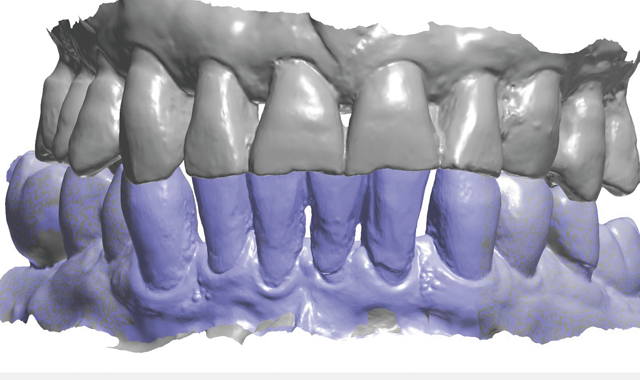

Treatment began by taking an intraoral 3D impression scan (3Shape TRIOS 3) (Fig. 4), after which a digital diagnostic “waxup” was created using Dental Designer (Fig. 5). Using digital intraoral scanning and digital “waxups” eliminated the need for time-consuming conventional impression taking, saving the patient time and eliminating discomfort. Additionally, proper shading, tooth size and contouring could be determined by examining and manipulating the digital impression/model images and

discussing the proposed changes with the patient.